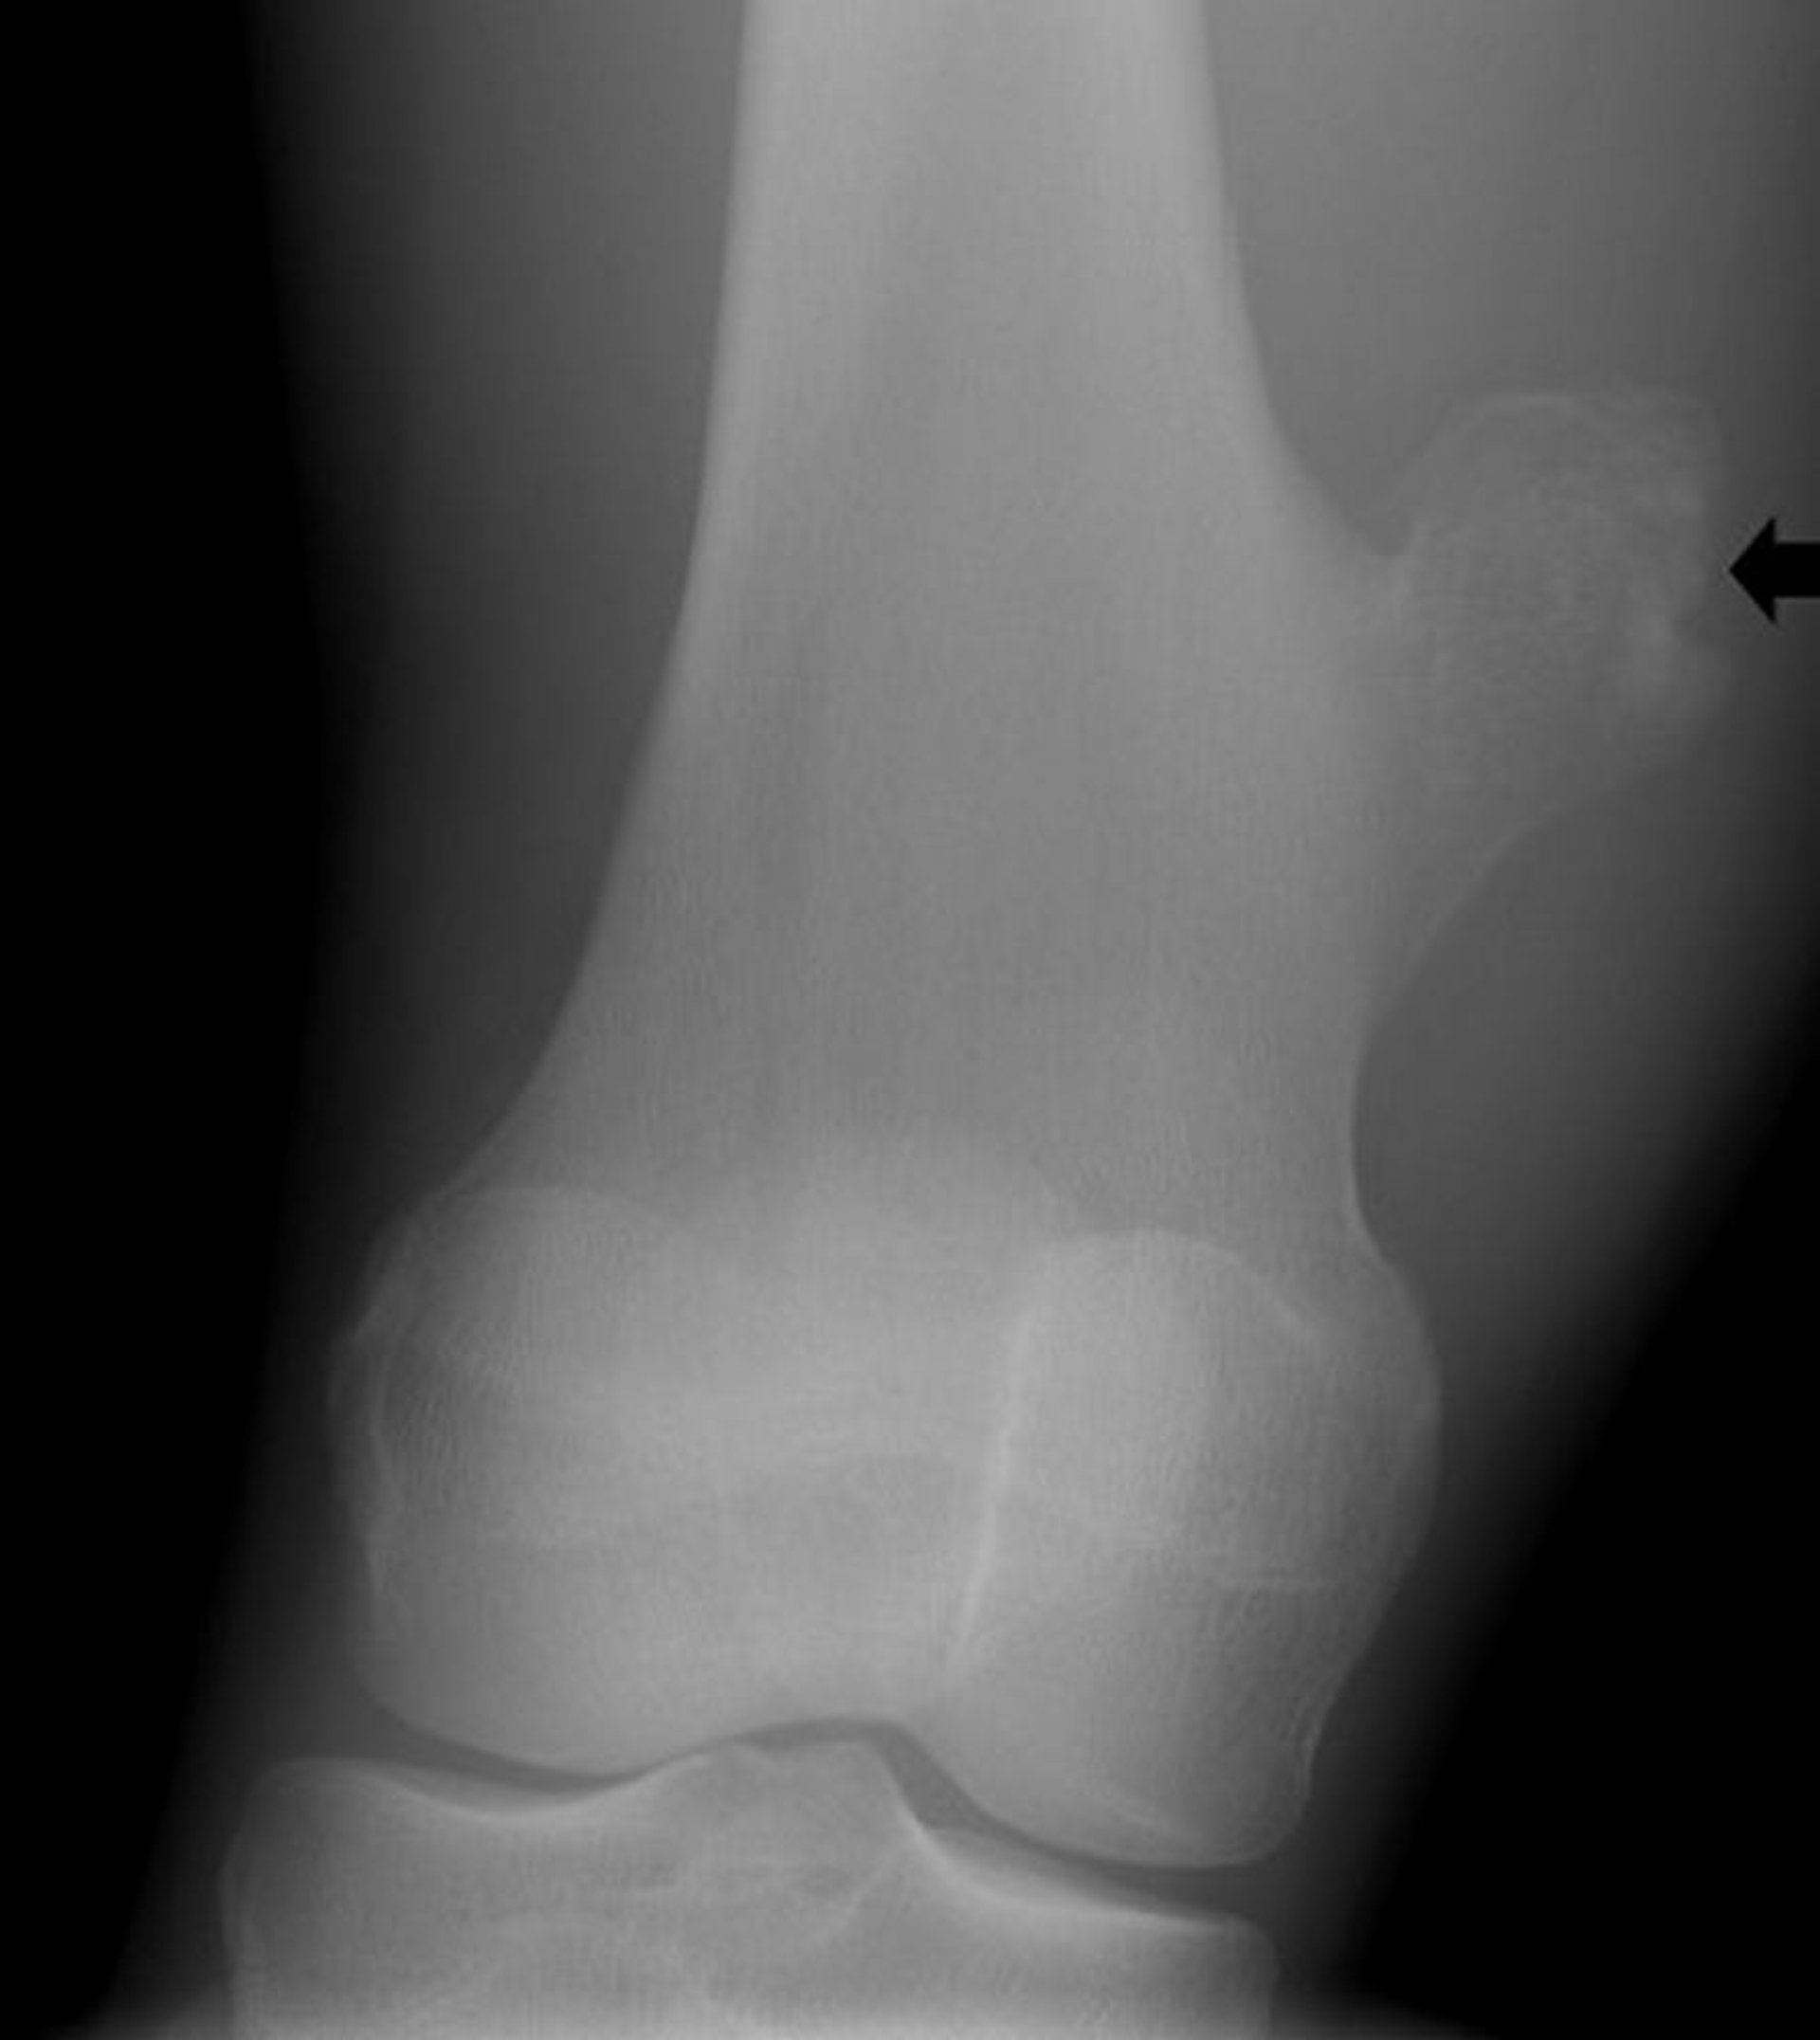

Osteocondroma do joelho

Essa radiografia do joelho mostra crescimento ósseo (seta) do fêmur acima da articulação do joelho, sugestiva de osteocondroma.

Imagem cedida por cortesia de Michael J. Joyce, MD, and Hakan Ilaslan, MD.